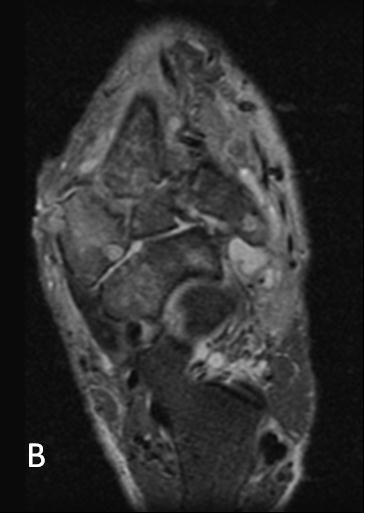

Figure 2A

T1-weighted (

A

) and T2-weighted (

B

) MRI scans depict diffuse intermedullary changes to the midtarsal bones with consolidated fragments, subluxations, and dislocations resulting in a gross deformity throughout the midfoot.Figure 2B

T1-weighted and T2-weighted MRI scans (Figure 2) depict diffuse intermedullary changes to the midtarsal bones with consolidated fragments, subluxations, and dislocations, resulting in a gross deformity throughout the midfoot.